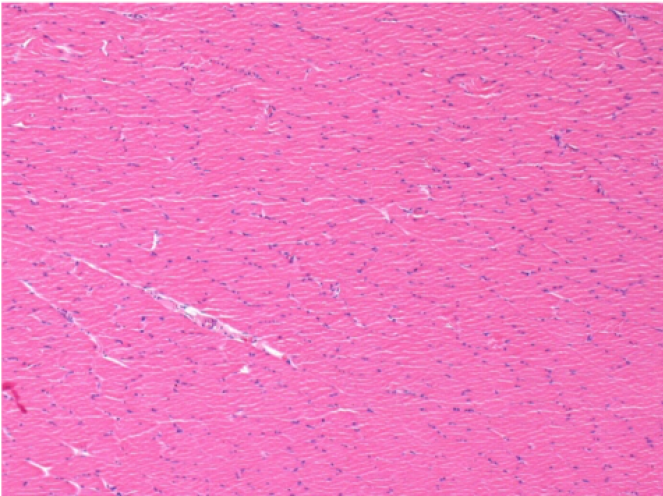

7 months (D210)after Endopeel IM Injection 0.1ml in the right pretibial muscle.

Complete Restitutio ad integrum after 7 months